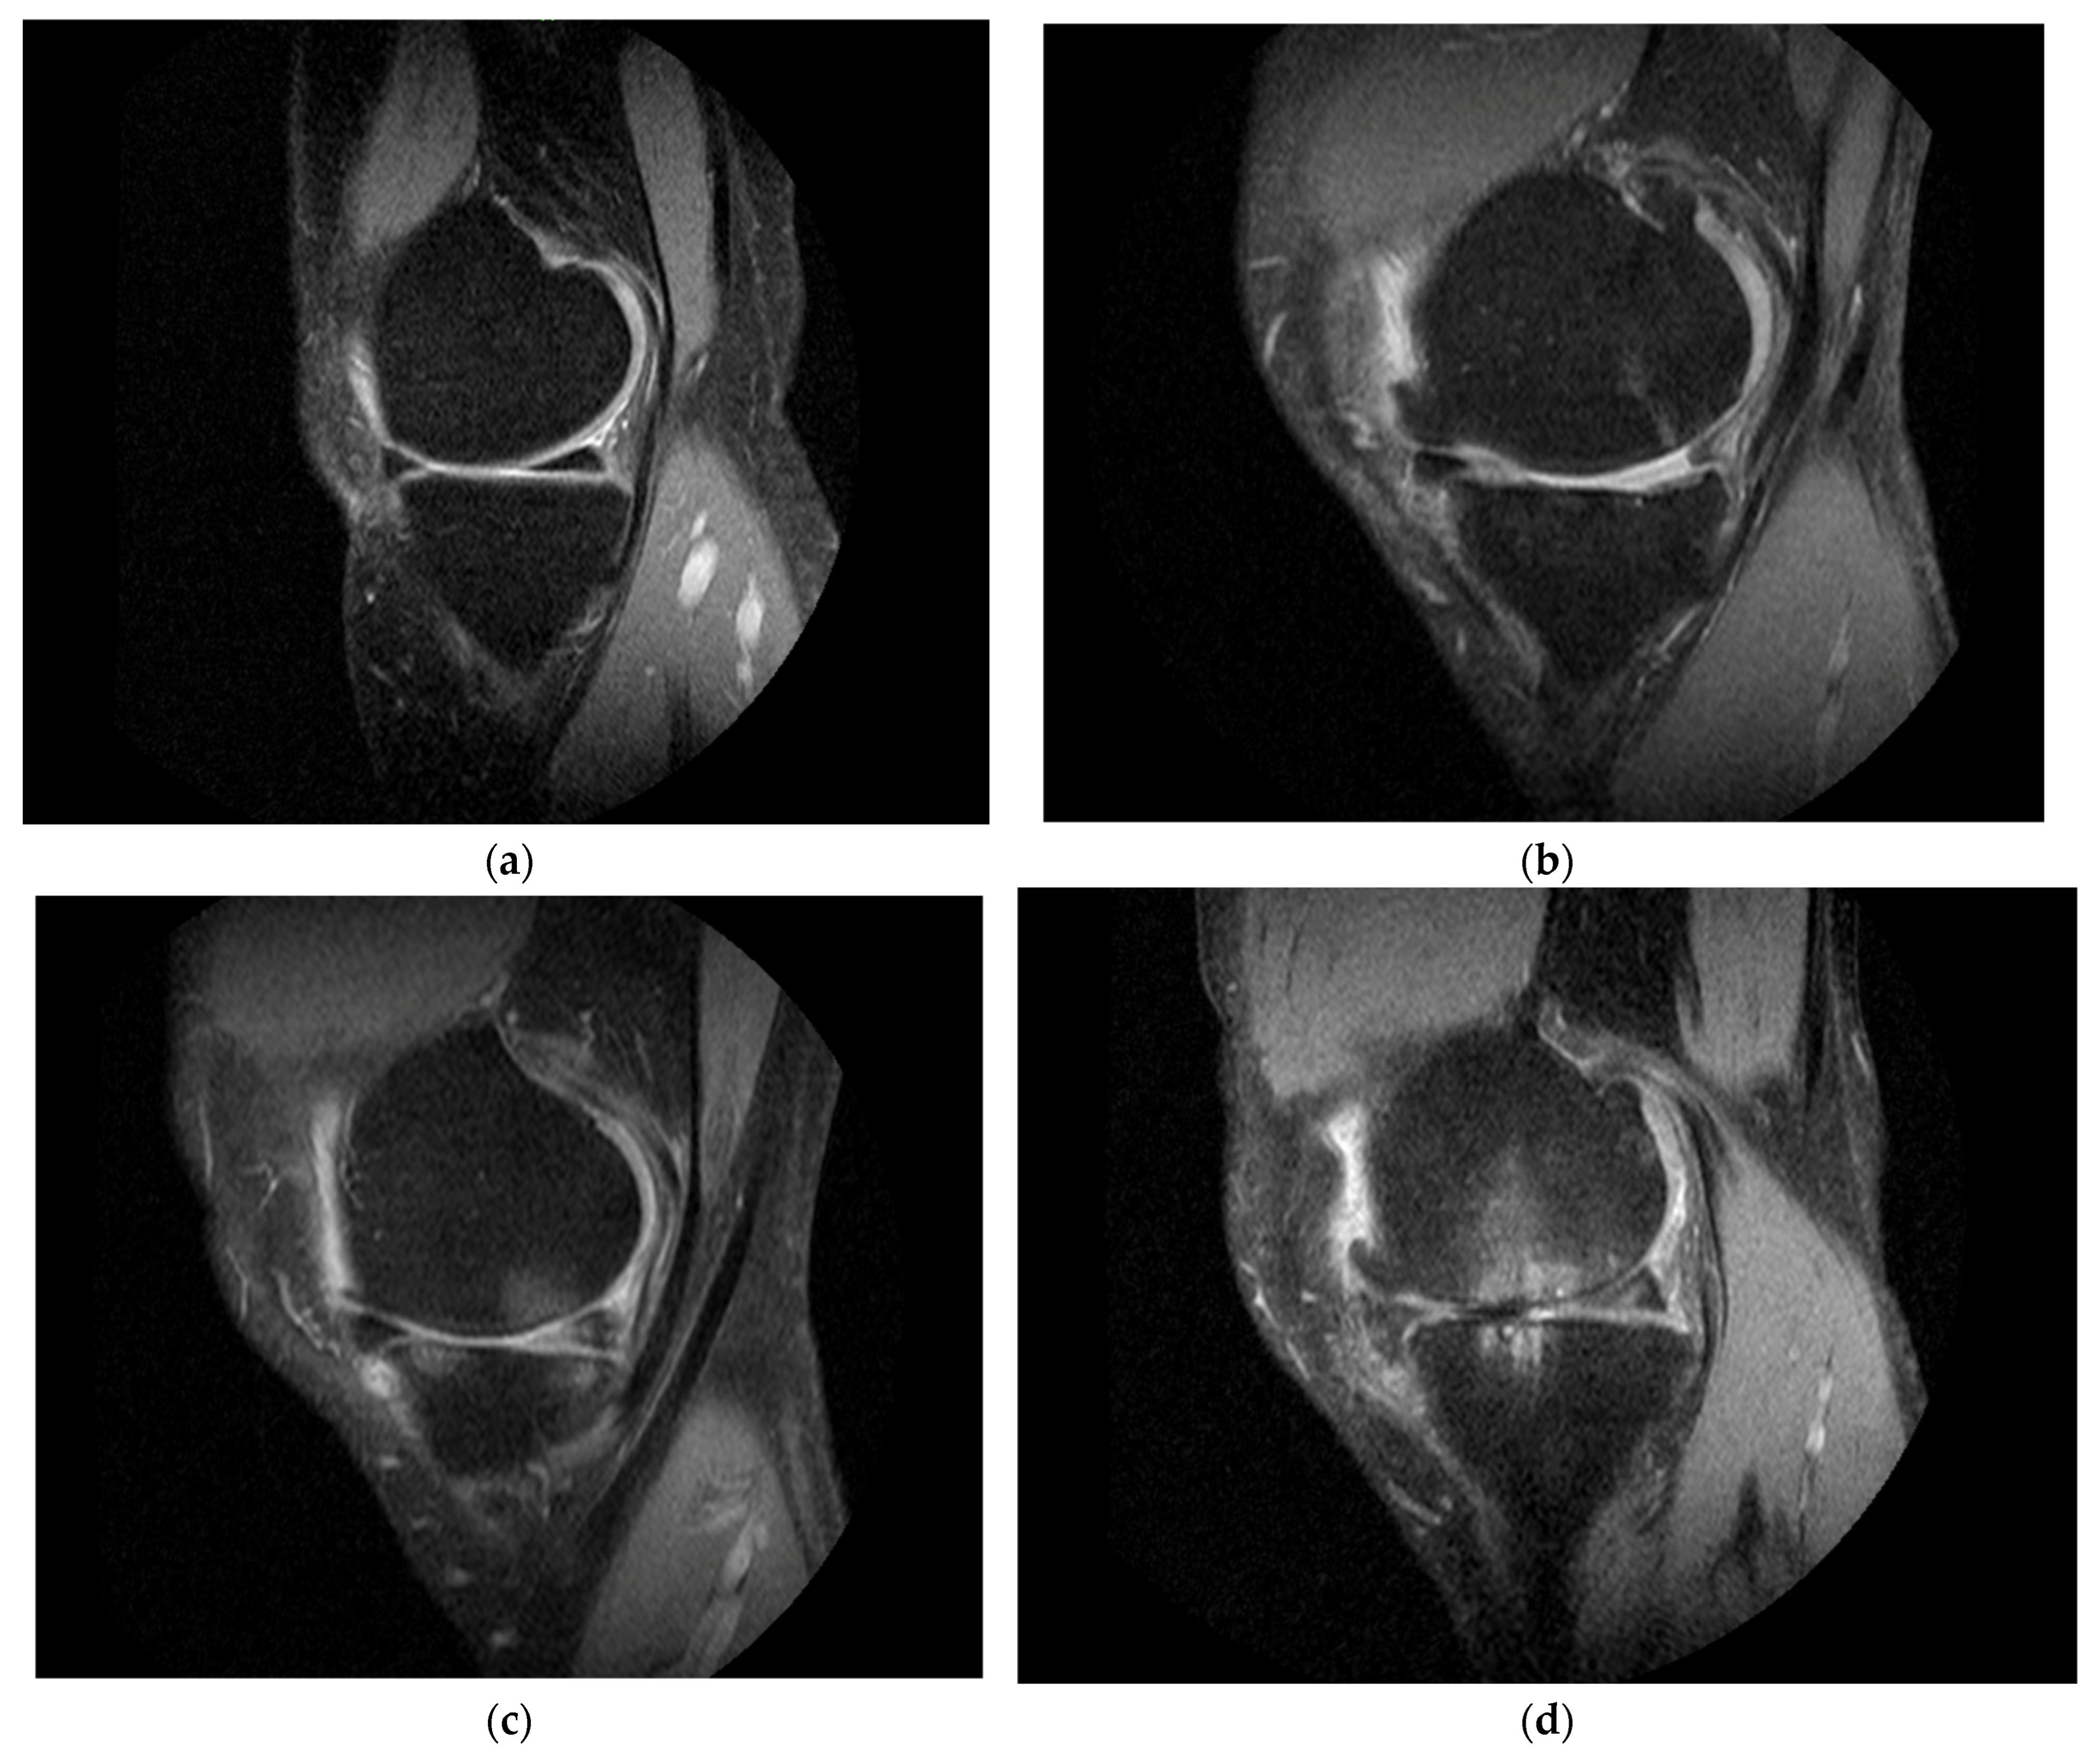

2.5. MRI Outcomes

4.3.2. MRI Outcome Measures